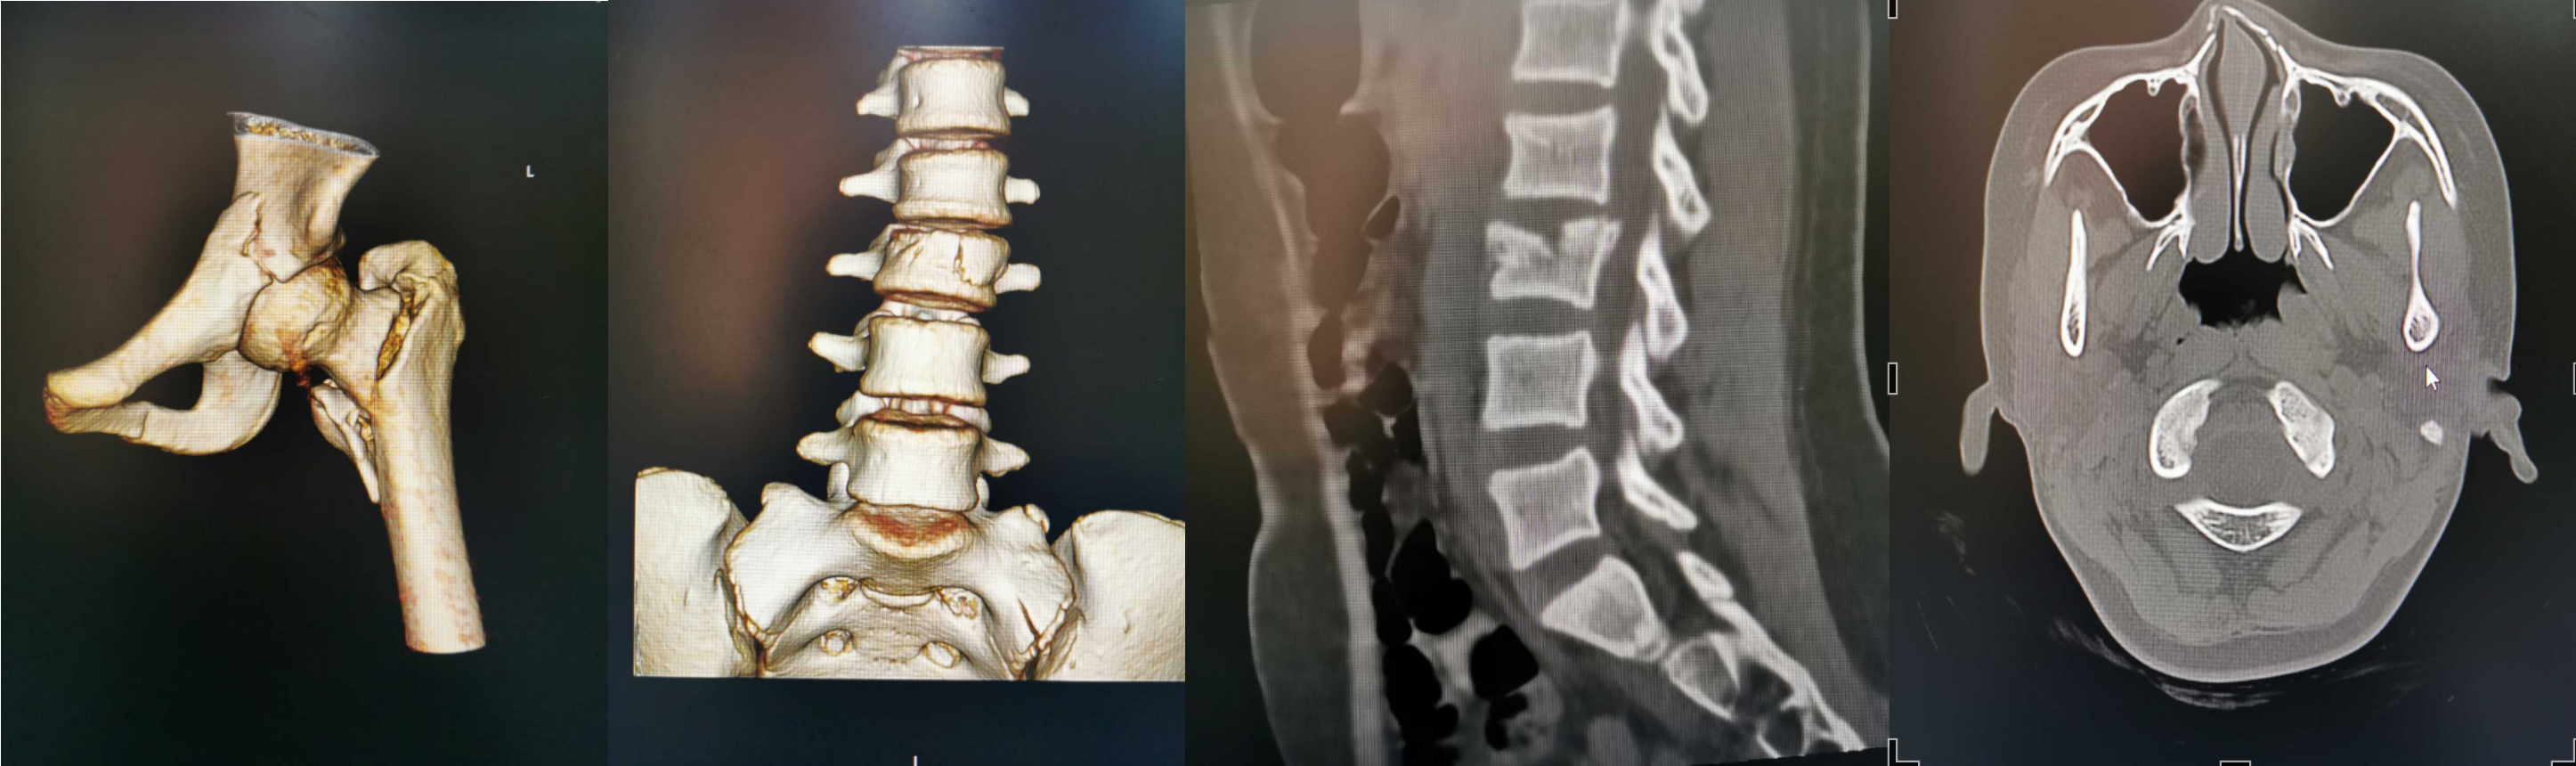

这是发生在2022年1月30日骨伤科病房的一幕。病床上小姑娘叫若琳(化名),是一位来自于广东罗定的12岁小姑娘,因为意外从高处跌落,导致腰椎骨折、髋部骨折、鼻骨骨折。面对复杂的多发骨折,加上家庭条件相对困难,若琳的父母心急如焚,经人联系,她从当地医院转被送到广州医科大学附属中医医院骨伤科救治。

骨伤科主任田天照副主任中医师第一时间组织专家进行全面评估,经过细致讨论,考虑到小女孩骨骺线未完全闭合,还有生长潜力,务必将手术对骨折生长发育的影响降到最低,科室最终制定了详细的治疗及护理方案。

经过手术,小若琳损伤最严重的髋部骨折得到了复位,良好的内固定位置既保证了骨折的稳定,又保留了骨骼发育的潜力。